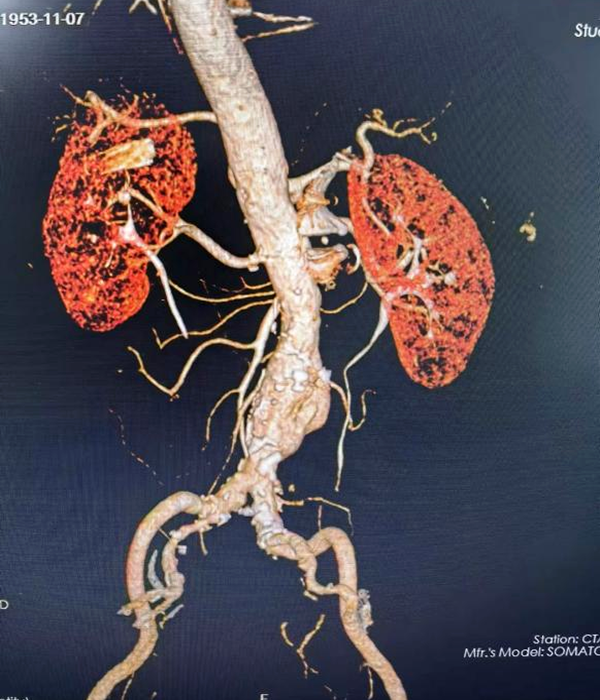

到达榆林二院后,急诊科立即启动绿色通道,行主动脉CTA检查后图像上发现患者腹腔内有大量出血,腹主动脉管壁已经不完整,此时患者腹痛难忍,命悬一线。胸外心脏大血管外科紧急进行术前准备后,在导管室对该患者行破裂腹主动脉瘤腔内修复手术,成功的为其拆除“不定时炸弹”。